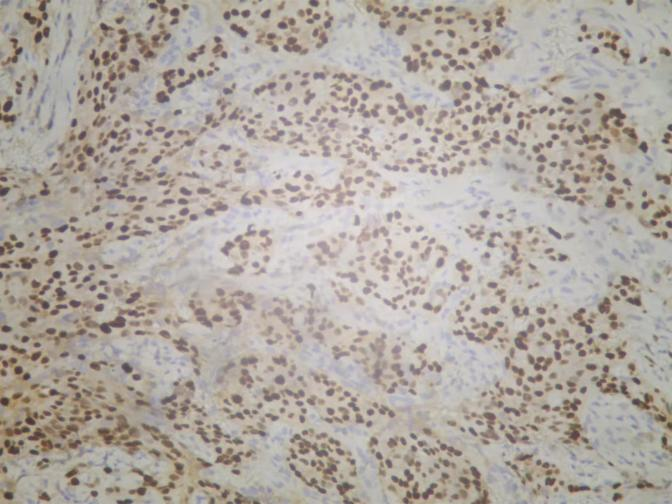

图4. 免疫组化PR

图5. 免疫组化ER

免疫组化结果:ER(中-强+,约80%),PR(强+,约90%),Cerb-B2(3+),Ki67(+,约40%)